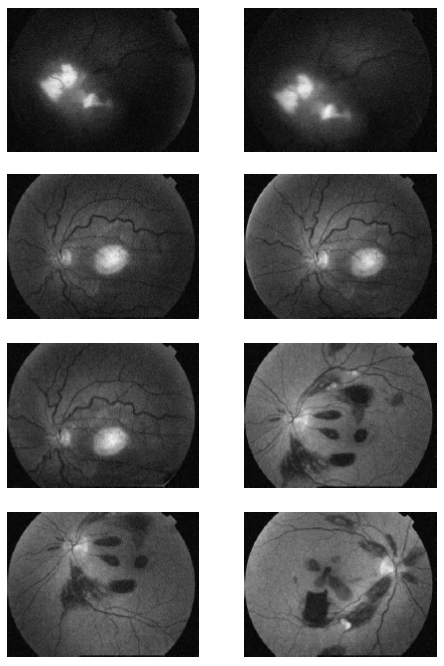

In the first part of the experiments, the effects of the score and penalty values for two iteration values were studied. All runs have been done for two neighborhood sizes of 3×3 and 5×5. Samples of the original retinal images with hard exudates are shown in (Figs. 1-3) show noisy images and the images denoised by the ripplet transform-based denoising method presented in this paper. Segmented images of retinal images are shown in Fig. (4). The images in Fig. (4) correspond to the implementation of the proposed method with a marginally optimum set of parameters, while their numerical results are given in Table 2. The results of statistical analysis on the score and penalty assignments are given in Table 2 while the proposed method is used with and without the denoising process. It is shown that the optimum score and penalty values stand about 0.01 and 0.02 while the product of score/penalty values and the number of iterations is important. The denoising process improves the statistical parameters of about 4-6%. It is also shown that for our dataset images, the neighborhood size of 5×5 which is an extended Moore neighborhood, leads to better results as compared to the simple Moore neighborhood.

![]() |

Fig. (1). Original Retinal Images with hard exudates. |

Fig.(2). Noisy Retinal Images with hard exudates (salt and pepper noise). |

Fig. (3). Denoised Retinal Images by cycle spinning and ripplet transform. |